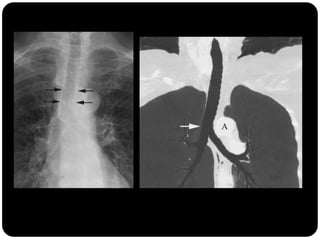

Vias aéreas

 Linha paratraqueal direita (interface do LSD

com parede lateral direita da traquéia): não

deve ultrapassar 4mm ;

 Parede paratraqueal esquerda circundada por

tecido adiposo e vasos mediastinais 

normalmente não é vista na radiografia;

Repare como a traquéia apresenta-se em um

exame em expiração...